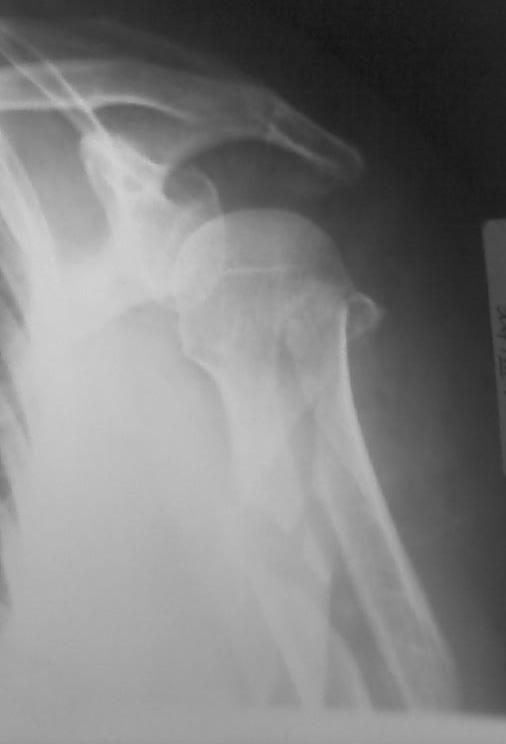

послал Евгений 09 Апрель 2009, 22:53

Высылаю рентгенограммы больной до операции и в гипсовой лонгете. Сейчас больную вообщем-то особо ничего не беспокоит, незначительная болезненность в области перелома при движениях плечом, первые два дня была отечность кисти, которая сейчас исчезла, объем движений в локтевом суставе постепенно увеличивается, отведение плеча пока небольшое. Дистальное блокирование выполнено одним винтом в передне-заднем направлении (через бицепс. Да, клинок мы конечно же заблокировали концевым колпачком. Нас тоже беспокоит возможность развития импиджмент синдрома, надеемся на то, что больная разработает движения в плечевом суставе.